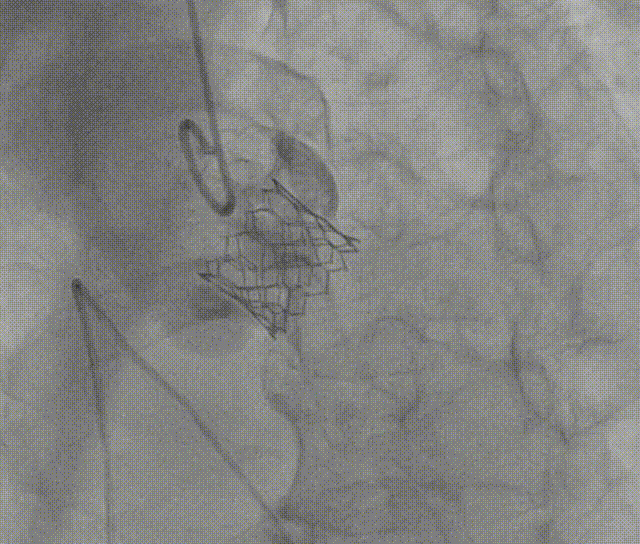

通过支撑导丝,送入26mm SAPIEN 3瓣膜,使用独特调弯功能,保证安全过弓并成功跨瓣;调整至共平面角度,瓣膜到位,快速起搏下-2cc精准释放瓣膜。

图片